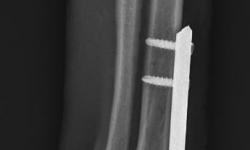

Pacient č. 3. - předoperační rtg.

Pacient č. 3. - použití implantátu Fixin Intrama.

Pacient č. 3. - pooperační rtg.

Pacient č. 3. - po operační rtg 2.

Pacient č. 3

• Plemeno sheltie, pohlaví fena, stáří 5 let

• Příčina kulhání –  úraz zápěstí z přetížení

• Diagnoza HEI – hyperextenzní poranění

• Terapie: PCA – pankarpální artrodéza